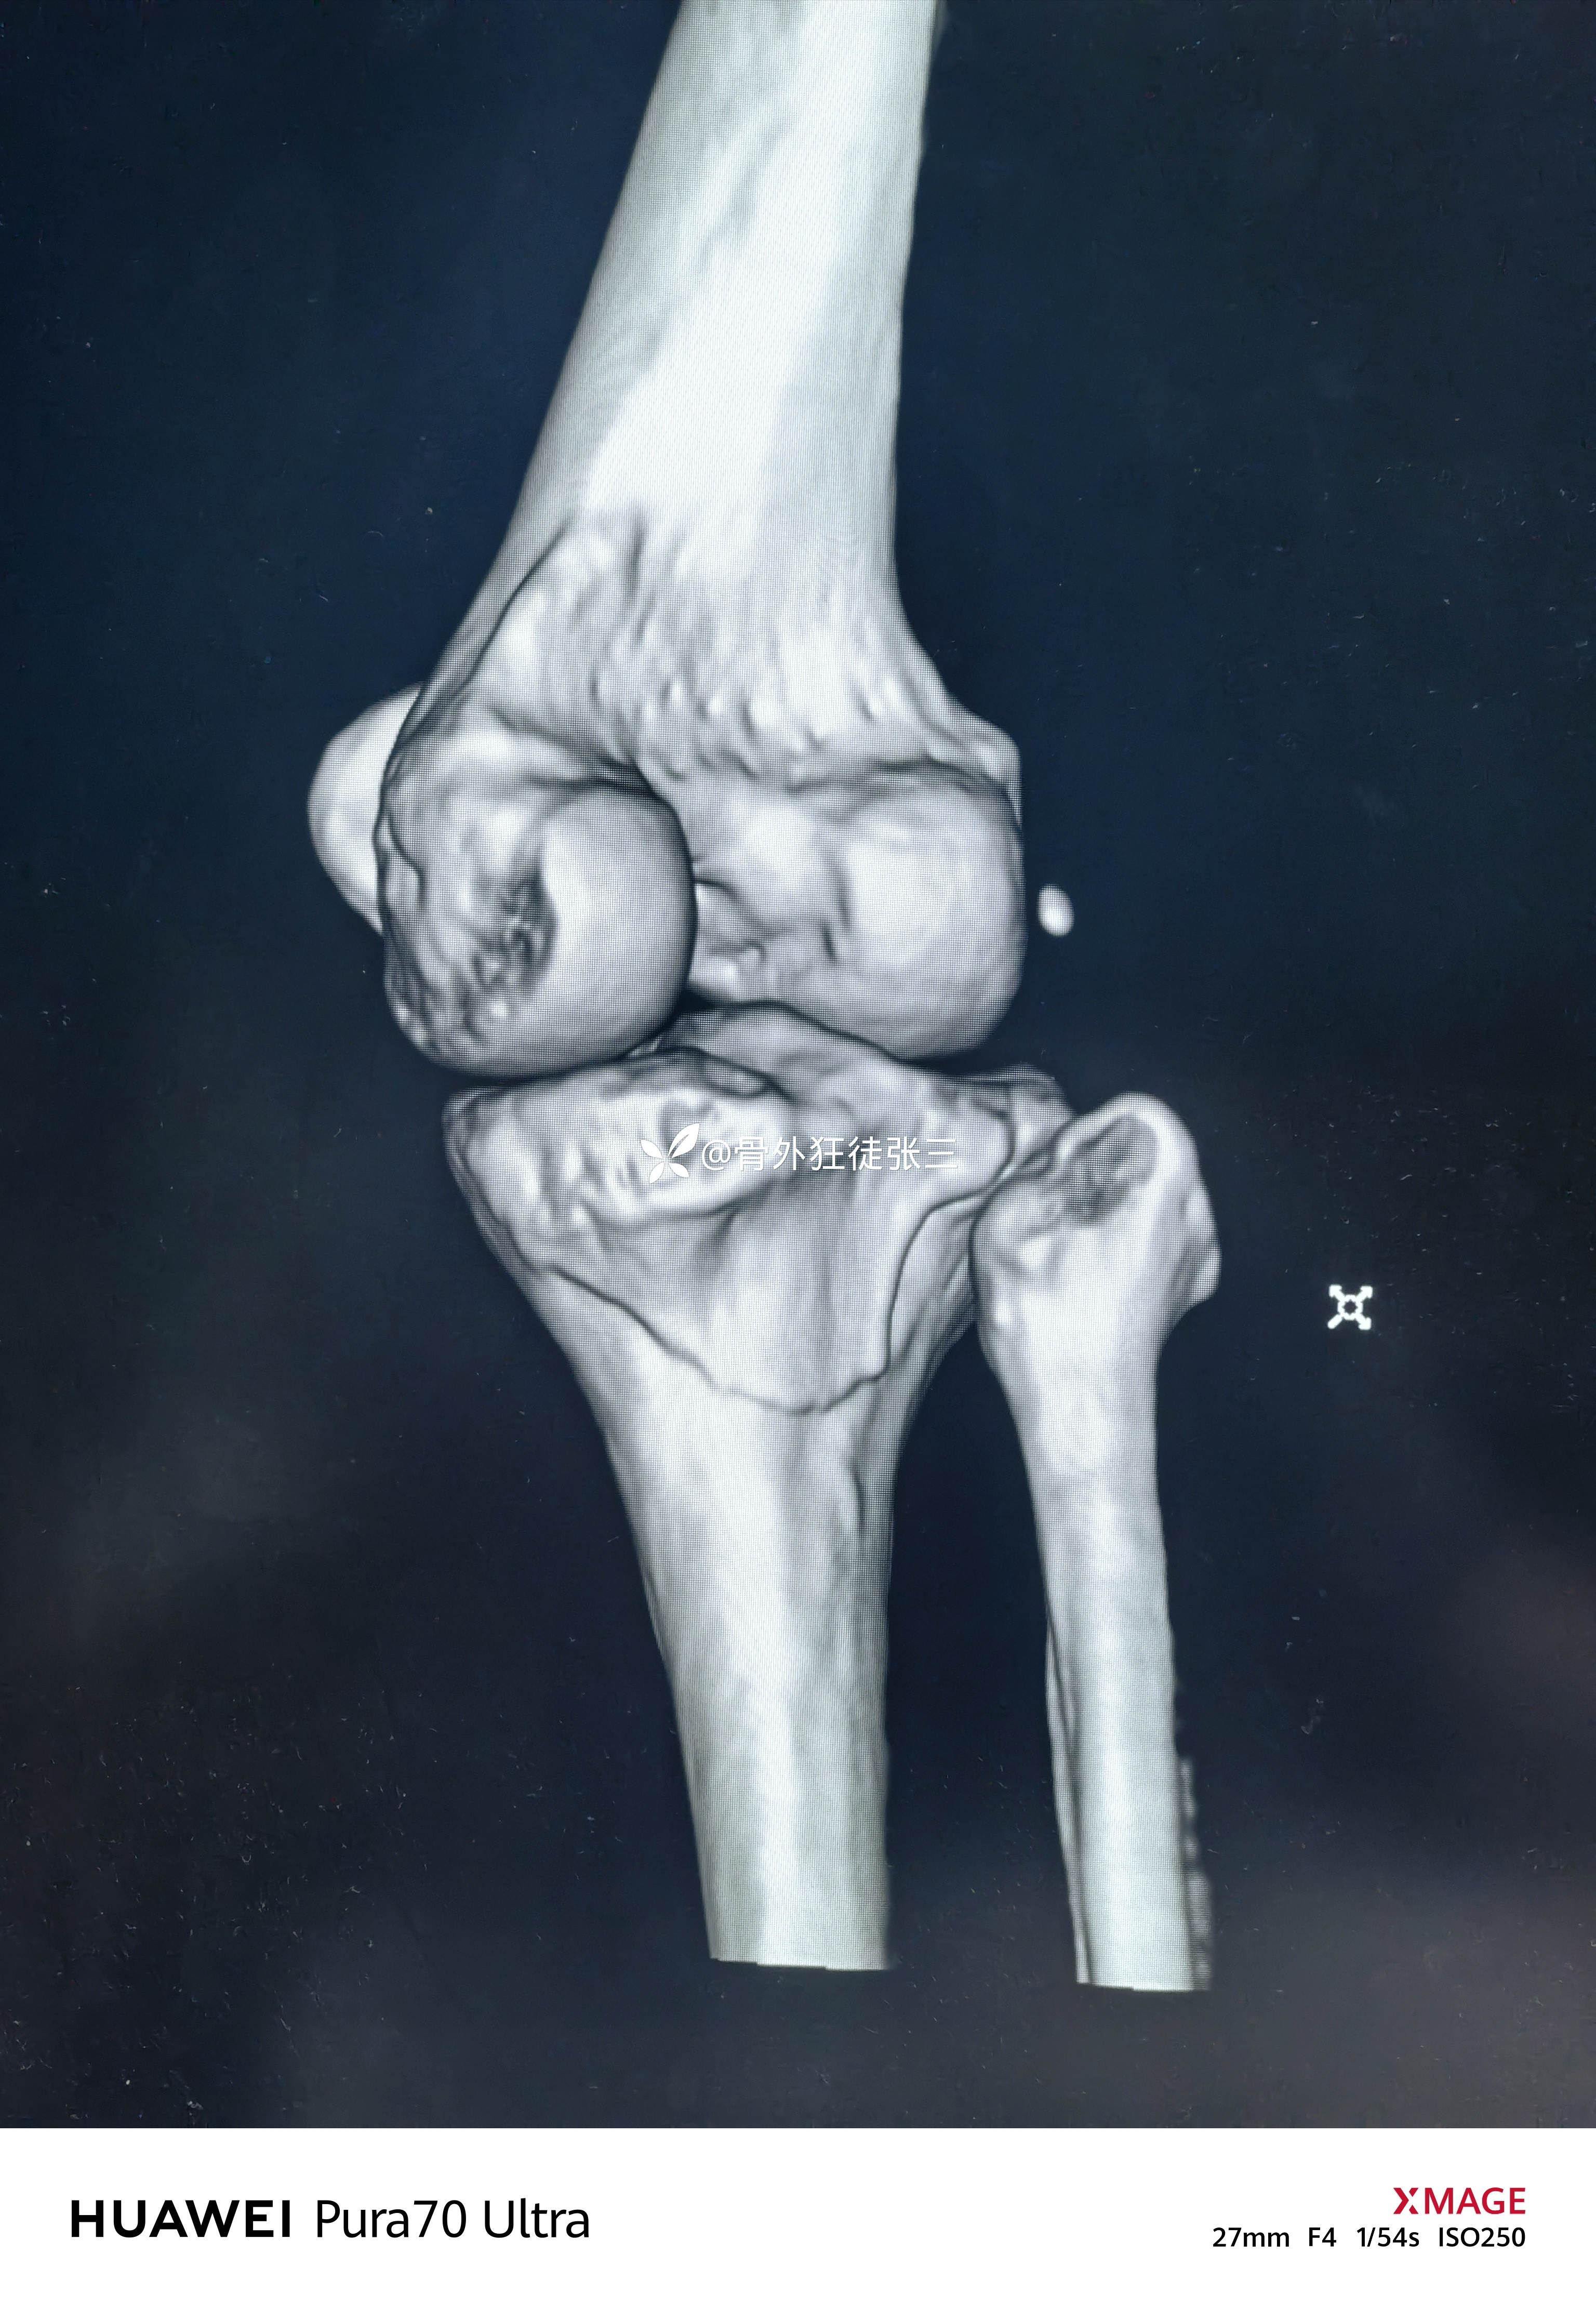

但是CT下显形惊涛骇浪

右胫骨平台骨折

(屈曲内翻型——后内侧平台骨折+外侧平台塌陷+ACL止点撕脱)